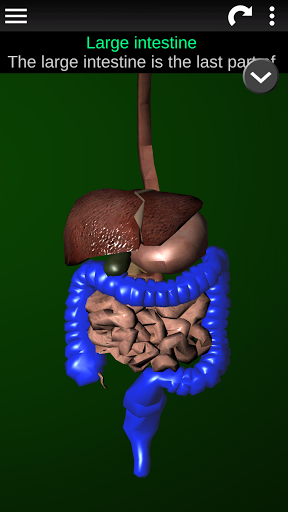

Shows a 3D anatomical model of the main organs of the human body and a description of each one.

* Digestive system, including the stomach, small intestine, large intestine, and an animation of this system.

* Easy to access and navigate (zoom, 3D rotation).

* Descriptions of each organ.